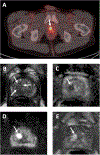

Purpose: Prostate-specific membrane antigen (PSMA)-targeting PET radiotracers reveal physiologic uptake in the urinary system, potentially misrepresenting activity in the prostatic urethra as an intraprostatic lesion. This study examined the correlation between midline 18 F-DCFPyL activity in the prostate and hyperintensity on T2-weighted (T2W) MRI as an indication of retained urine in the prostatic urethra.

Patients and methods: Eighty-five patients who underwent both 18 F-DCFPyL PSMA PET/CT and prostate MRI between July 2017 and September 2023 were retrospectively analyzed for midline radiotracer activity and retained urine on postvoid T2W MRIs. Fisher's exact tests and unpaired t tests were used to compare residual urine presence and prostatic urethra measurements between patients with and without midline radiotracer activity. The influence of anatomical factors including prostate volume and urethral curvature on urinary stagnation was also explored.

Results: Midline activity on PSMA PET imaging was seen in 14 patients included in the case group, whereas the remaining 71 with no midline activity constituted the control group. A total of 71.4% (10/14) and 29.6% (21/71) of patients in the case and control groups had urethral hyperintensity on T2W MRI, respectively ( P < 0.01). Patients in the case group had significantly larger mean urethral dimensions, larger prostate volumes, and higher incidence of severe urethral curvature compared with the controls.

Conclusions: Stagnated urine within the prostatic urethra is a potential confounding factor on PSMA PET scans. Integrating PET imaging with T2W MRI can mitigate false-positive calls, especially as PSMA PET/CT continues to gain traction in diagnosing localized prostate cancer.